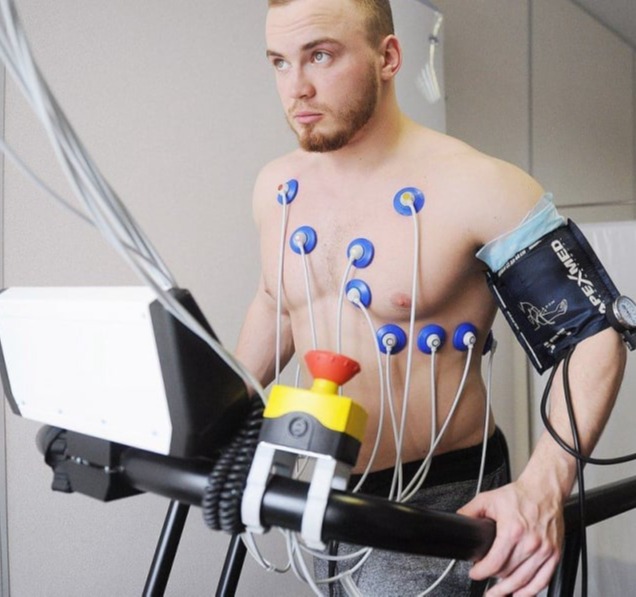

24ωρη καταγραφή της πίεσης (Holter Πίεσης)

Η 24ωρη καταγραφή της αρτηριακής πίεσης, επίσης γνωστή ως Holter Πίεσης, είναι ένας ειδικός τύπος εξέτασης που χρησιμοποιείται για την παρακολούθηση των επιπέδων αρτηριακής πίεσης κατά τη διάρκεια μιας ολόκληρης ημέρας και νύχτας. Αυτή η διαδικασία παρέχει λεπτομερείς πληροφορίες σχετικά με τα επίπεδα πίεσης κατά τη διάρκεια των καθημερινών δραστηριοτήτων και του ύπνου.

Η εξέταση πραγματοποιείται με τη χρήση ενός μικρού φορητού συσκευή, γνωστής ως Holter, η οποία συνδέεται στον ασθενή και καταγράφει αυτόματα την αρτηριακή πίεση κατά τη διάρκεια του 24ωρου περιόδου. Ο ασθενής συνεχίζει τις καθημερινές του δραστηριότητες και καταγράφει οποιεσδήποτε συμπτώματα ή δραστηριότητες σε ημερολόγιο.

Οι πληροφορίες που παρέχει η 24ωρη καταγραφή της πίεσης συμπεριλαμβάνουν τα μεγέθη και τις διακυμάνσεις της συστολικής και διαστολικής πίεσης, την αντίδραση της πίεσης σε διάφορες καταστάσεις (όπως κατά τη διάρκεια ύπνου, κατά τη διάρκεια άσκησης, κλπ.) και τυχόν ανωμαλίες που ενδέχεται να εμφανιστούν.

Αυτή η εξέταση είναι χρήσιμη για τη διάγνωση και την παρακολούθηση της υπέρτασης, καθώς και για την αξιολόγηση της απόκρισης στη θεραπεία. Επιπλέον, μπορεί να βοηθήσει στην ανίχνευση ανωμαλιών που δεν ανιχνεύονται εύκολα με τις συνηθισμένες μετρήσεις πίεσης κατά την επίσκεψη στον ιατρό.